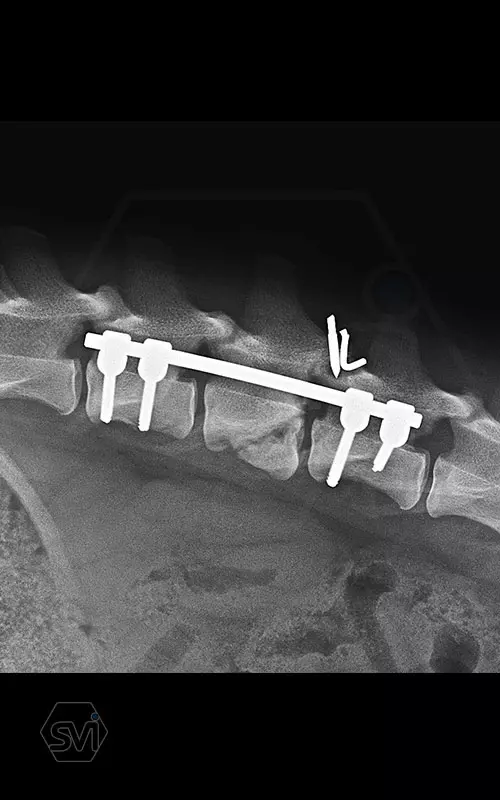

Kutya neve: Benetton, az SOP-LC hatékonysága és stabilitása magáért beszél, a gyógyulás alatt a gerinc folyamatos terhelés alatt volt, és a fémek nem mozdultak el. A kutya szerencsére neurológiailag i felépült! Tehát van esély a gerinctörések esetén is a gyógyulásra...